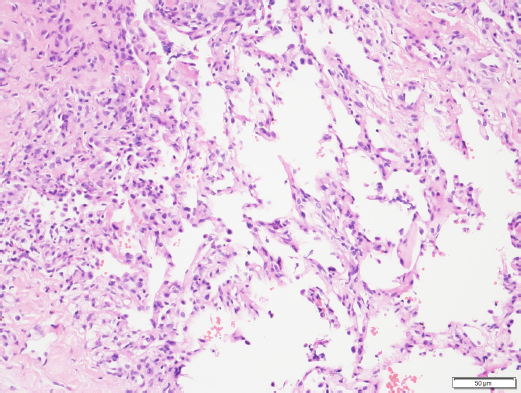

Histopathologic results of the sample confirmed marked, multifocal, chronic, neutrophilic, and eosinophilic granulomatosis with a fibrous capsule (Figs. 4 and 5).

Histochemical stains including, Gram for bacteria, Ziehl-Neelsen for acid-fast organisms, Periodic Acid–Schiff, and Grocott Methenamine Silver for detection of fungal organisms, were applied to the tissue sampled and all failed to reveal any infectious agents. A negative bacterial culture supported the results observed in histochemistry. The result was consistent with pulmonary pyogranuloma compatible with EPG. Corticosteroid treatment was started with a daily dose of prednisolone (Macrolone, Mavlab) at 2 mg/kg PO q 24 hours for 2 weeks.

Fig. 5. Histopathology of the pulmonary mass. Fibrosis, eosinophilic multifocal inflammation and alveolar septa (200× oil magnification). Image courtesy of Dr. May TSE from CityU VDL, Hong Kong.